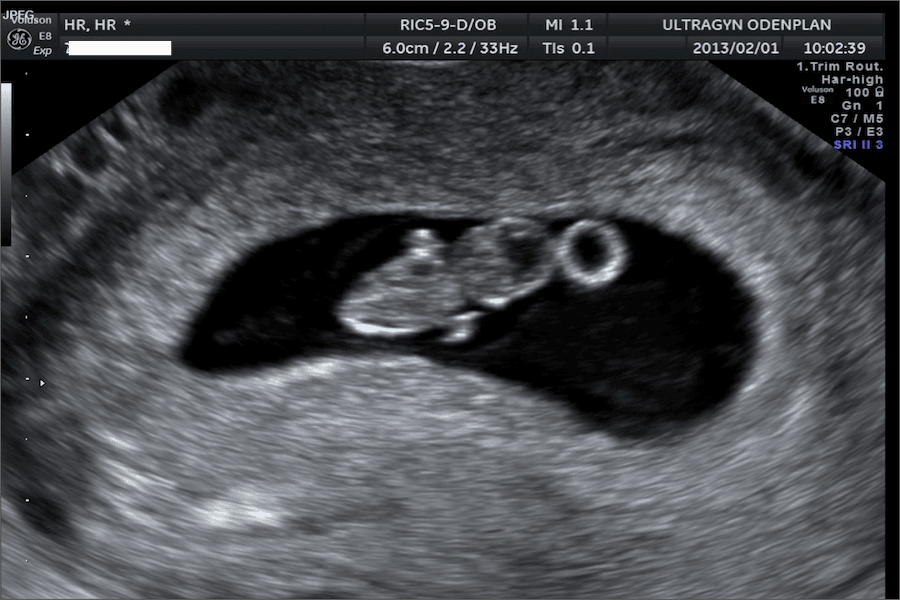

En tidlig ultralyd er en scanning, der foretages et sted mellem uge 6 og 12. Denne type ultralyd udføres for at bekræfte, at graviditeten er levedygtig (altså at der er hjerteaktivitet), at graviditeten sidder korrekt i livmoderen, hvor mange børn der er derinde, samt for at forsøge at fastsætte graviditetslængden. Nogle gange er det for tidligt at beregne graviditetslængden, og så vil du blive anbefalet en ny ultralyd et par uger senere.

Hvis der er set hjerteaktivitet på en tidlig ultralyd før uge 8, mindskes risikoen for spontan abort, og efter uge 12 er risikoen for spontan abort lav. Hvis du tidligere har oplevet spontan abort eller andre komplikationer, kan det føles betryggende at bede om en ultralyd i tidlig graviditet.